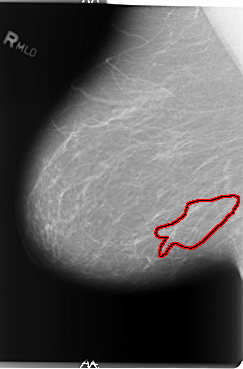

FILE: B_3011_1.RIGHT_MLO.OVERLAY

TOTAL_ABNORMALITIES 1

ABNORMALITY 1

LESION_TYPE CALCIFICATION TYPE PLEOMORPHIC-FINE_LINEAR_BRANCHING DISTRIBUTION LINEAR-SEGMENTAL

ASSESSMENT 4

SUBTLETY 3

PATHOLOGY MALIGNANT

TOTAL_OUTLINES 1

BOUNDARY